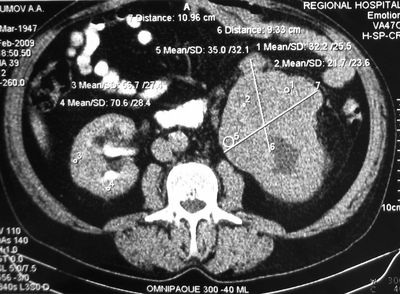

Опухоль левой почки